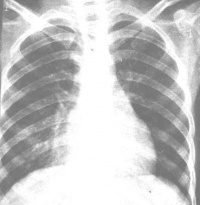

腺病毒性肺炎透视

应根据流行情况,结合临床进行诊断。典型婴幼儿腺病毒肺炎早期与一般细菌性肺炎不同之处为:①大多数病例起病时或起病不久即有持续性高热,经抗生素治疗无效;②自第3~6病日出现嗜睡、萎靡等神经症状,嗜睡有时与烦躁交替出现,面色苍白发灰,肝肿大显著,以后易见心力衰竭惊厥合并症。上述症状提示腺病毒肺炎不但涉及呼吸道,其他系统也受影响;③肺部体征出现较迟,一般在第3~5病日以后方出现湿性罗音,病变面积逐渐增大,易有叩诊浊音及呼吸音减低,喘憋于发病第二周日渐严重;④白细胞总数较低,绝大多数病儿不超过12×109/L(12000/mm3),中性粒细胞不超过70%,中性粒细胞的碱性磷酸酶四唑氮蓝染色较化脓性细菌感染时数值明显低下,但如并发化脓性细菌感染则又上升;⑤X线检查肺部可有较大片状阴影,以左下为最多见。总之,在此病流行季节遇有婴幼儿发生较严重的肺炎,且X线和血象也比较符合时,即可作出初步诊断。有条件的单位,可进行病毒的快速诊断。目前可进行免疫荧光技术(间接法较直接法更为适用)、酶联免疫吸附试验及特异性IgM测定,唯此三种方法均不能对腺病毒进行分型,是其不足之处。而常规咽拭子病毒分离及双份血清抗体检查,只适用于实验室作为回顾诊断。

2.X线检查

X线形态与病情、病期有密切关系。肺纹理增厚、模糊为腺病毒肺炎的早期表现。肺部实变多在发病第3~5天开始出现,可有大小不等的片状病灶或融合性病灶,以两肺下野及右上肺多见。发病后6~11天,其病灶密度随病情发展而增高,病变也增多,分布较广,互相融合。与大叶肺炎不同之处是,本病的病变不局限于某个肺叶。病变吸收大多数在第8~14天以后。有时若病变继续增多、病情增重,应疑有混合感染。肺气肿颇为多见,早期及极期无明显差异,为双侧弥漫性肺气肿或病灶周围性肺气肿。1/6病例可有胸膜改变,多在极期出现胸膜反应,或有积液